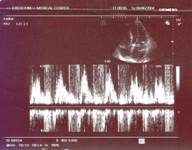

Эхокардиография (18 июня 2004): дилатация всех полостей сердца, ЛП = 4,8 см, КДРЛЖ = 5,8 см, ПЖ = 3,2 см. Гипертрофия миокарда обоих желудочков. Аорта уплотнена, в восходящем отделе не расширена. АК: створки уплотнены, противофаза не нарушена. МК: передняя створка, после ее средней части флотирует, асинхронно движется, по сравнению с ее основанием и средней частью, задняя створка уплотнена, амплитуда ее раскрытия не снижена. Зон локальных асинергий нет.

Рис. 1

Рис. 2

Наблюдается гиперкинезия межжелудочковой перегородки. Общая сократимость снижена за счет выраженной митральной регургитаций. ФВ = 50–52%. Допплер: митральная регургитация 3–4 степени, трикуспидальная регургитация 2 степени.

Для уточнения диагноза и лучшей визуализации структурных изменений митрального клапана была произведена трансэзофагеальная эхокардиография (9 июня 2004г.): визуализация удовлетворительная. Oпределяется флотация передней створки митрального клапана, отмечается отрыв одной из сухожильных хорд. Допплер: митральная регургитация 3-4 степени, трикусидальная регургитация 2 степени. Регургитирующая струя в левом предсердии доходит до первой легочной вены. Давление в легочной артерии - 50 мм рт.ст. Дилатация левого предсердия: ЛП = 5 см, ПЖ = 3,2 см.